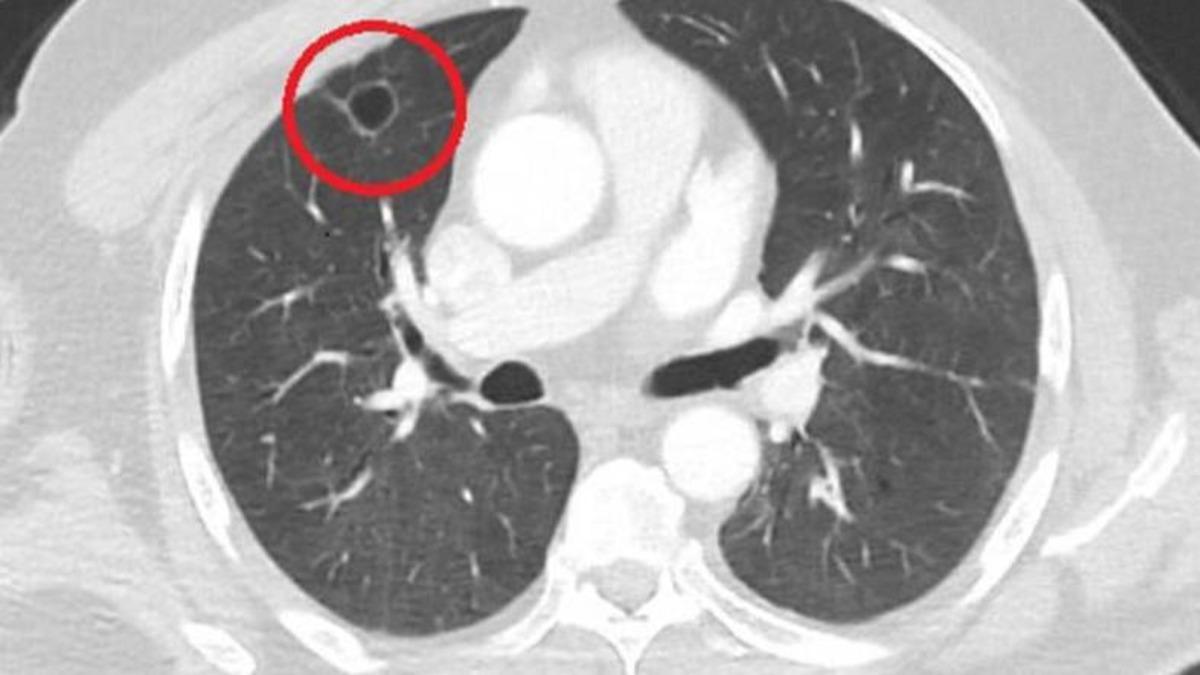

Sütçü İmam Üniversitesi Sağlık Uygulama ve Araştırma Hastanesi Göğüs Cerrahi Anabilim Dalı Öğretim Üyesi Dr. Fatoş Kozanlı da hasta için tomografi ve testler sonrası akciğer kanseri teşhisi koydu ve ameliyat gerektiğini söyledi. Gireceği operasyon öncesi PCR testi yapılan N.T.'nin testi pozitif çıktı ve COVID-19 tedavisi için ameliyat 14 gün ertelendi. Tedavi sürecinden sonra PCR testi negatif çıkan N.T. ameliyata alınmadan önce yeniden çekilen tomografide akciğerdeki tümörün tamamen yok olduğu tespit edildi.

Kozanlı hastanın durumunu "Hastamız, çalıştığı başka bir kentte göğsünden darbe alıyor ve ağrıları geçmeyince bir üniversite hastanesine başvuruyor. Burada hastaya bir akciğer grafisi çekiliyor. Sağ akciğerinde bir kitleye rastlanıyor. Daha sonra hastaya, bir akciğer tomografisi çekiliyor ve göğüs cerrahisi için önemli büyüklükte olan 4 santimetre çapında, akciğer kanserine benzer özellikte radyolojik bulgular olan bir kitle tespit ediliyor. Daha sonra hastaya yapılan ileri tetkiklerde akciğer kanseri teşhisi konuluyor. Hastaya bir cerrahi planlanıyor. Hasta Kahramanmaraşlı olduğu için kendi memleketine gelmeyi tercih ediyor. Bize başvurdu ve göğüs ağrısı şikayeti vardı. Öksürük, nefes darlığı, balgam çıkarma, ateş gibi şikayetleri yoktu. Hastayı biz de değerlendirdik ve ameliyat olmasına karar verdik. Çünkü akciğer kanserine çok benzer radyolojik bulguları vardı. Sağlık Bakanlığımızın kuralları gereği her hastayı ameliyat öncesi PCR testi yapılır. Biz de ameliyat gecesi hastadan PCR testi aldık ve testi pozitif geldi. Ameliyatımızı 14 gün erteledik ve hastamıza koronavirüs tedavisi uygulandı. Hasta 14'üncü gün tekrar bize başvurdu ve yapılan PCR testi negatif çıktı. Yeni bir tomografi çektik ve tümörün tamamen ortadan kalktığını gördük. Şimdi sonuç bilgilerinden başlangıca gittiğimizde, bu bir akciğer kanseri olsaydı, ortadan kalkması mümkün değildi. Başka bir patolojiye bağlı durum olsaydı, yine verdiğimiz tedaviyle ortadan kalkmasını çok beklemeyiz. Antiviral tedavisi verdik ve hastanın radyolojik bulguları neredeyse tamamen normale döndü. Hastaya bunu izah ettik, 'Dünya literatüründe hiç görülmeyen bir radyolojik bulgu' diyerek. Bu gördüğümüz manzara artık hastanın akciğer grafisinde yok, akciğer kanseri değil'' sözleriyle açıklarken varılan sonucun şaşırtıcı olduğunu ifade ediyor.